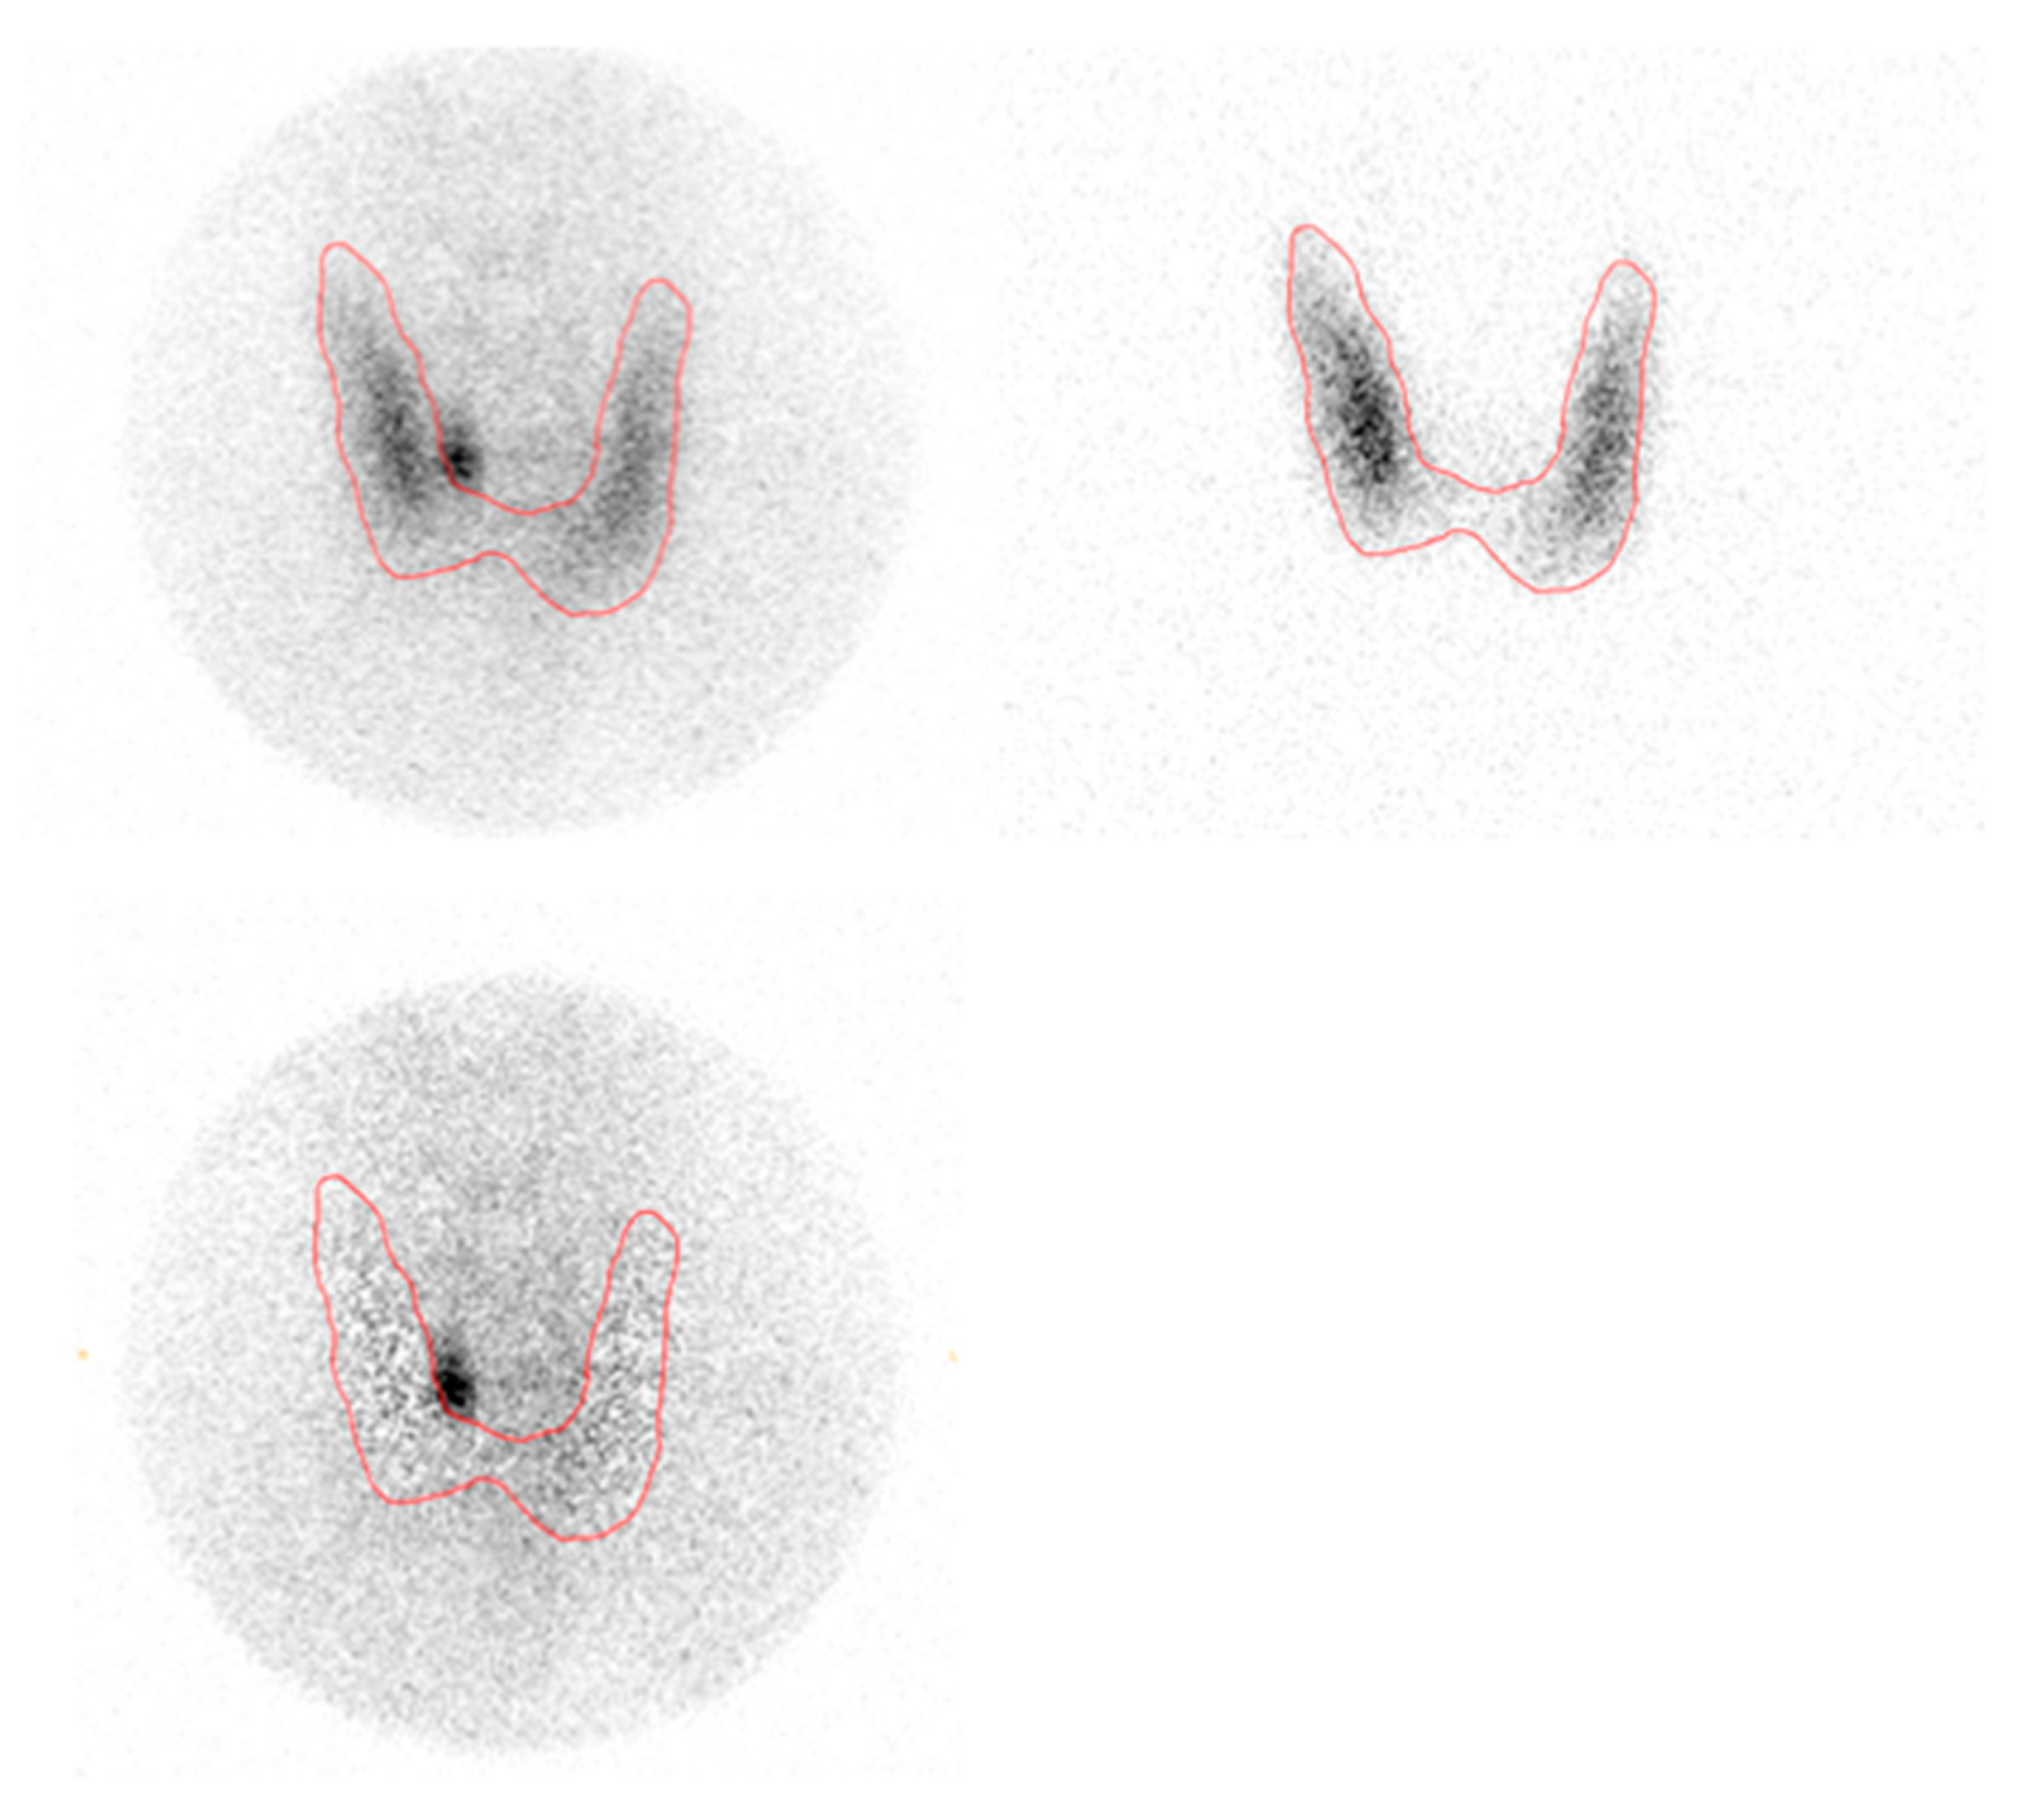

See Figure 1 and Figure 2 for images (same patient as Figure 3).

Figure 1. Dual isotope planar pinhole subtraction scintigraphy. Upper left: 99mTc-sestamibi pinhole. Upper right: 123I pinhole. Bottom left: Pinhole subtraction.